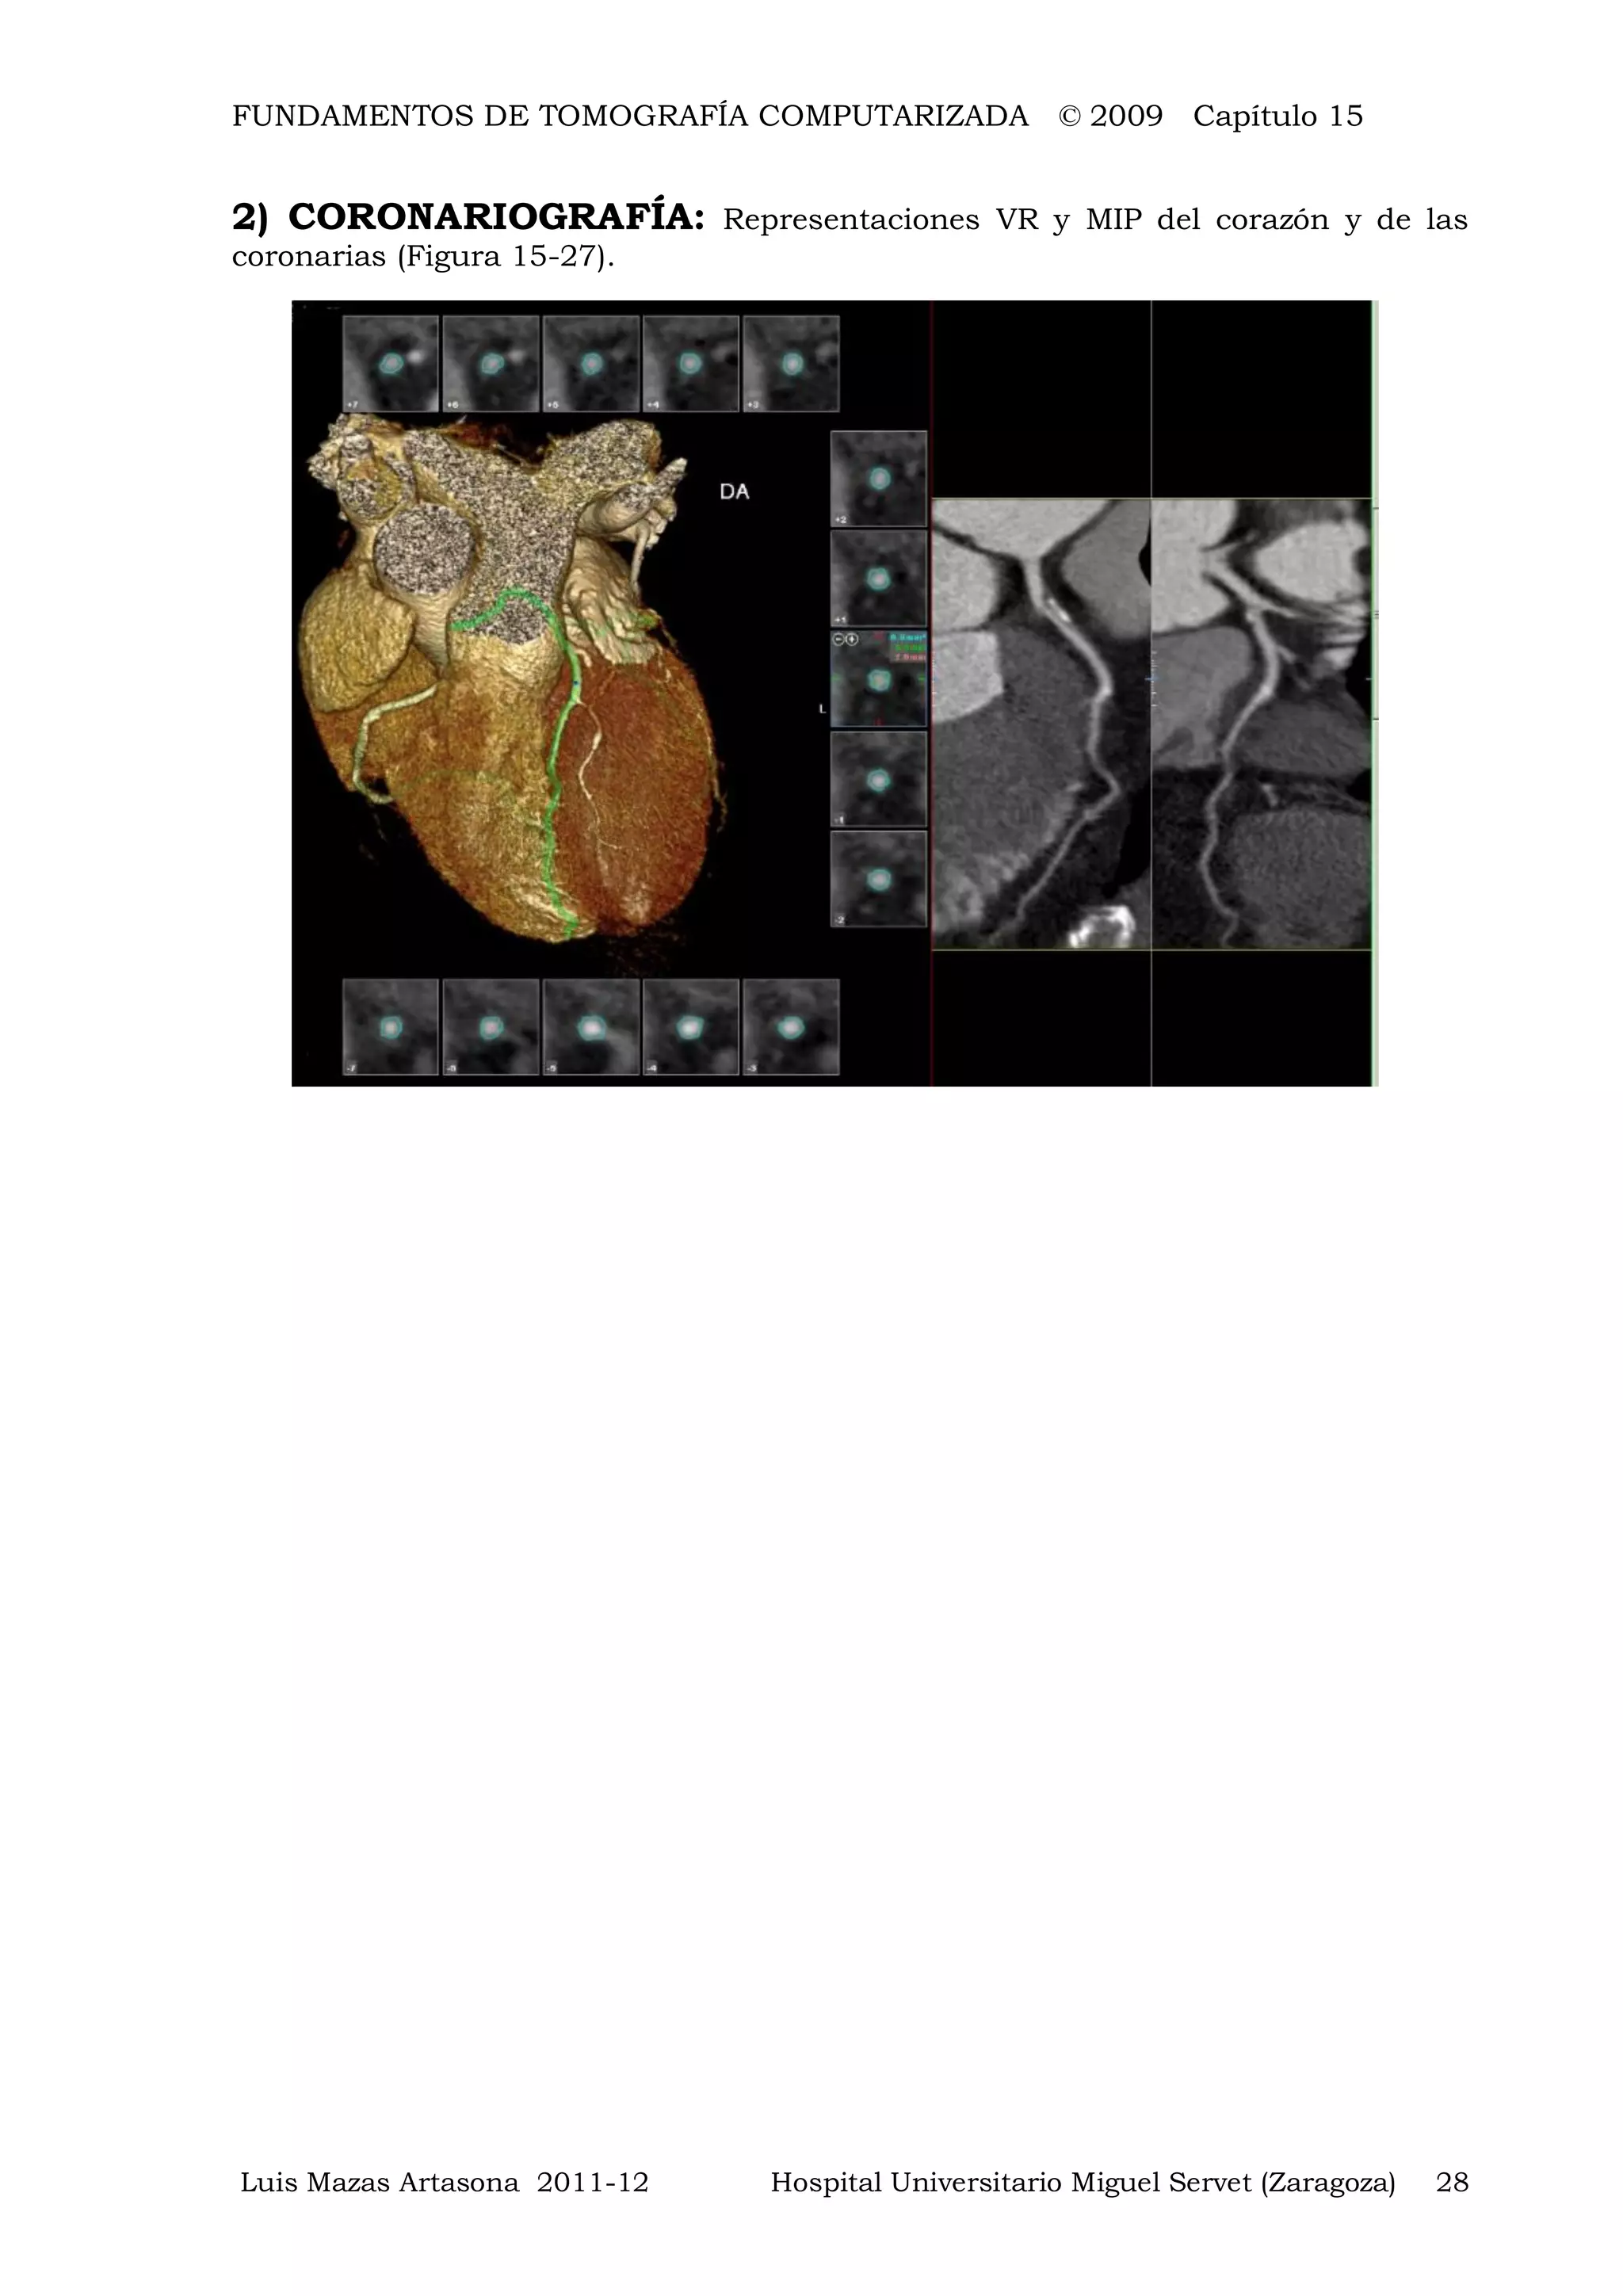

2) CORONARIOGRAFÍA: Representaciones VR y MIP del corazón y de las

coronarias (Figura 15-27).